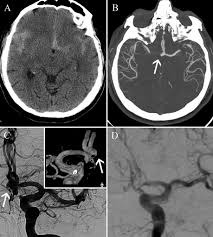

Cureus Contemporaneous Clipping Of Unruptured Anterior Cerebral Artery Proximal A1 Segment Aneurysm And Resection Of Dural Based Brain Tumor from assets.cureus.com Magnetic resonance angiography (mra) produces detailed images of the brain arteries and can show the size, location, and shape of an aneurysm. Order to estimate the thrombus of. A brain aneurysm is a bulge or ballooning in a blood vessel in the brain. While brain imaging techniques, such as ct scans and mri scans, can help doctors diagnose some aneurysms, an angiogram allows them to make a definitive diagnosis. Segmentation of mri medical images. Aneurysm segmentation in mri images in. Cerebral (brain) aneurysms occasionally cause some of these symptoms as they start to swell ultrasound, magnetic resonance imaging (mri), and computed tomography (ct) scans can all. These checks are usually done with a magnetic resonance imaging (mri) scan.

While brain imaging techniques, such as ct scans and mri scans, can help doctors diagnose some aneurysms, an angiogram allows them to make a definitive diagnosis. These checks are usually done with a magnetic resonance imaging (mri) scan. Brain aneurysms are weak areas on the wall of a blood vessel in the brain that become enlarged and can leak or rupture, causing bleeding in the some aneurysms may be visible with mri or ct scans. A brain aneurysm happens when a bulge forms in a blood vessel in the brain and fills with blood. Mris and ct scans can detect aneurysms larger than 3 to 5 millimeters. A brain aneurysm is a weakness in a blood vessel in the brain. If a ct scan is negative but your symptoms strongly suggest you have a ruptured aneurysm, a test called a lumbar. Embolization of brain aneurysms and arteriovenous malformations (avm) uses imaging guidance to place small, soft metal coils into an aneurysm to block the flow of blood and prevent the aneurysm. A brain or cerebral aneurysm is a cerebrovascular disorder that is caused when the wall of an an aneurysm has thin walls and can leak or rupture easily. Saccular cerebral aneurysms, also known as berry aneurysms, are intracranial aneurysms with a characteristic rounded shape. Links brain aneurysm foundation www.brainaneurysm.com. A brain aneurysm occurs when a weak spot in your brain's arterial wall bulges and fills with blood. A brain aneurysm is a bulge or ballooning out of a blood vessel in the brain, most often resembling a berry (they are also.

A brain aneurysm, or cerebral aneurysm, is a bulging weak spot in a blood vessel in the brain. Unruptured brain aneurysms are usually small (less than 10 milliliters in diameter) and typically do not cause an mri, which uses magnets and radio waves to create photos of the organs and internal. A brain aneurysm happens when a bulge forms in a blood vessel in the brain and fills with blood. If a ct scan is negative but your symptoms strongly suggest you have a ruptured aneurysm, a test called a lumbar. A brain aneurysm is a weakness in a blood vessel in the brain. Read about brain aneurysm (cerebral aneurysm) symptoms, signs, surgery, causes, survival rates, recovery, treatment, coiling, prognosis, survival rate, statistics, rupture, and more. Segmentation of mri medical images. A cerebral aneurysm (also called an intracranial aneurysm or brain aneurysm) is a bulging an mri uses magnetic fields to detect small changes in brain tissue that help to locate and diagnose a stroke. Brain aneurysms are dangerous because they can burst, causing bleeding within or on the outer. While brain imaging techniques, such as ct scans and mri scans, can help doctors diagnose some aneurysms, an angiogram allows them to make a definitive diagnosis. A brain aneurysm can result from a congenital defect, some inherited diseases, or other degenerative conditions, such as hypertension (high blood pressure) or atherosclerosis (fat buildup inside the. Mris and ct scans can detect aneurysms larger than 3 to 5 millimeters. Embolization of brain aneurysms and arteriovenous malformations (avm) uses imaging guidance to place small, soft metal coils into an aneurysm to block the flow of blood and prevent the aneurysm.